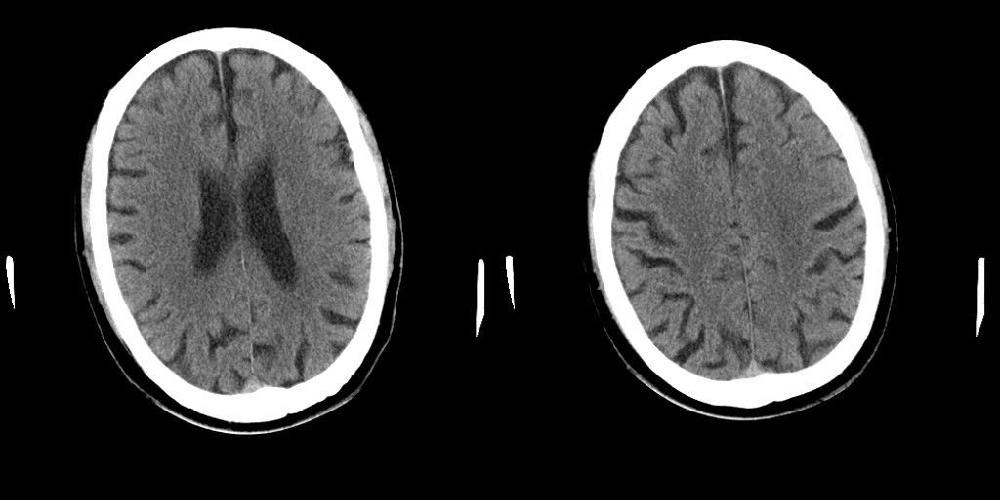

标题: CT25311:箭头所指是问题么?

该患者因头疼来诊,发现枕骨不规则缺损。

蛛网膜颗粒压迹,讨论过很多了,年龄大了不考虑lch;脑白质疏松。

蛛网膜颗粒压迹。脑萎缩。